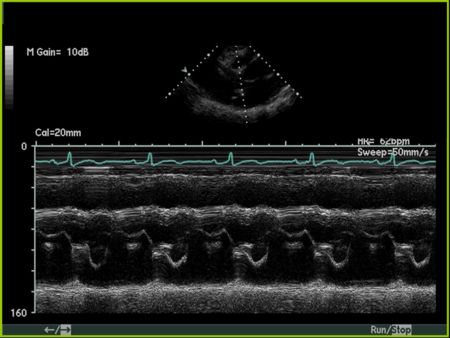

Aortic Valve M-mode Analysis

- During systole do the aortic valve leaflets oppose the aorta?

- Are the leaflets thick and calcified (bright)?

- Possible to have normal appearance on m-mode if non-calcific

- Are leaflets open throughout systole - HOCM, low-output state